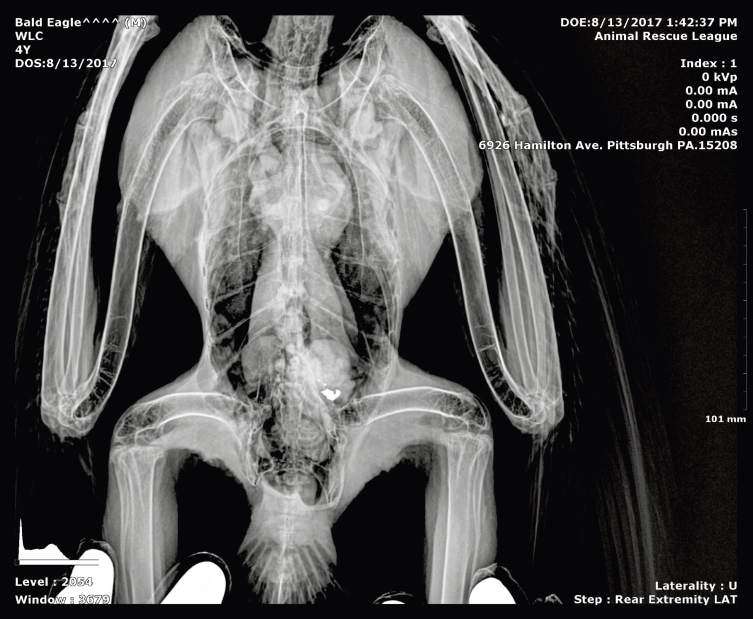

Kiski's lead poisoning was caused by a metal object in his stomach, something he had eaten recently, according to Carol Holmgren, executive director of the Tamarack wildlife center.